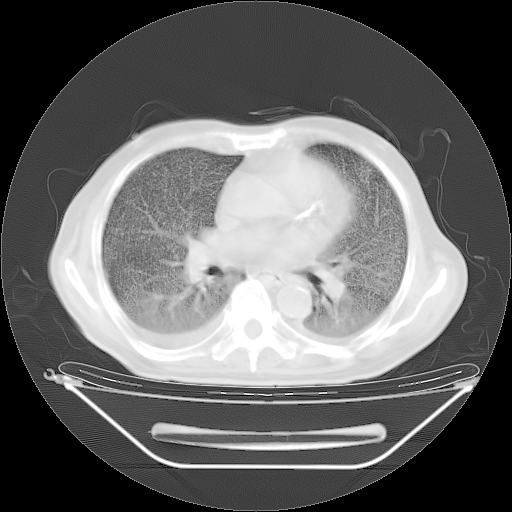

胸腹部CT,诊断意见:左上肺叶钙化灶、左侧胸膜局限性增厚并钙化、胆囊炎。描述部分肺组织呈磨玻璃样改变。